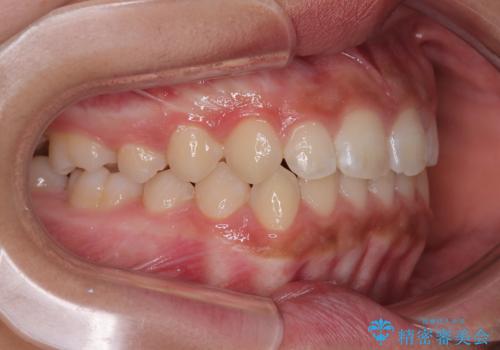

気になるすきっ歯を短期間で改善 インビザライン矯正

- 前歯の隙間を気にして来院された患者様です。

口元の突出感があり、小臼歯4本を抜歯して口元を引っ込める矯正治療も提案しましたが、本人は口元の突出感は気になっていないとのことで、インビザラインにて隙間やデコボコを改善することとしました。

軽度の歯列不正であったため、廉価版のインビザライン・モデレートパッケージにて治療を終えることができました。